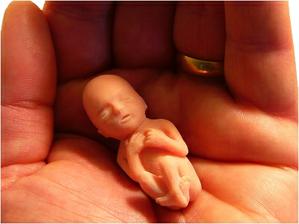

některé obrázky čerpány z http://mimiblog.cz/kt/tyden/1

zázrak lidské života na videu